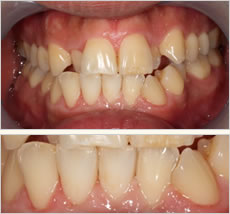

After

初診時と比べてプラークコントロールが改善され、ほとんどプラークの付着が見られません。歯ぐきが赤く腫れあがっていたのが引き締まりピンク色になってきています。